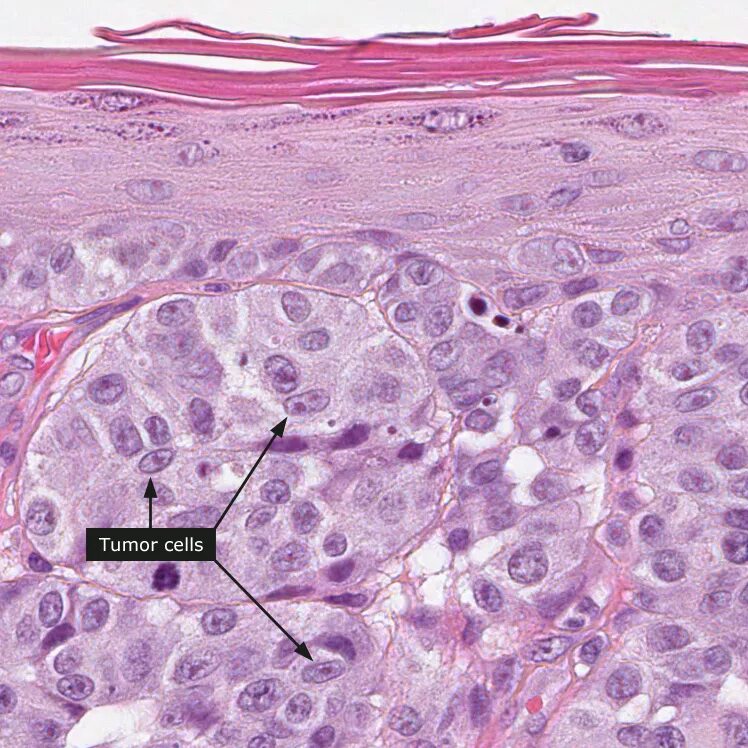

Гистология сложная